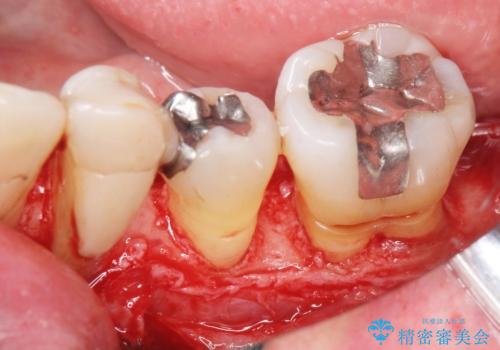

骨吸収の進行している左下臼歯部に、再生療法(骨を増やす手術))を行いました。

再生療法から1年後、リエントリー手術により骨の再生を確認し、骨外科処置(骨を平らにして歯周ポケットの根本的な改善を図る処置)を行いました。